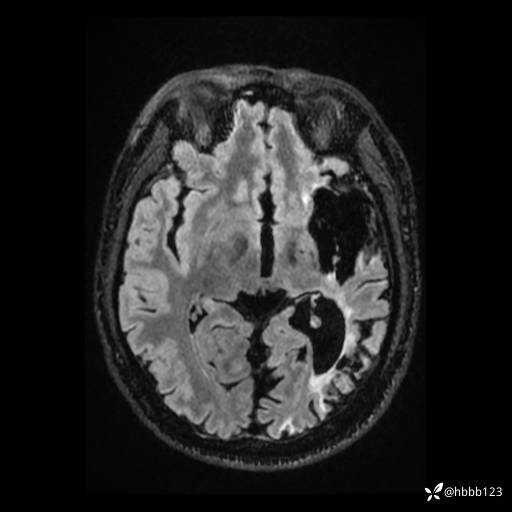

T2: